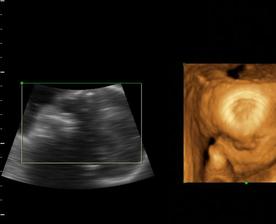

a z Emy Silvie je nkoniec Natalka...teraz uz 4 a pol roka, netrpezlivo cakajuca na braceka, ktory restie v brusku...🙂